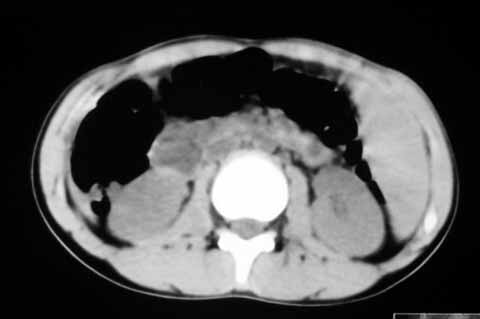

以下是引用zhangzhongshou在2007-5-22 21:04:00的发言:[br]1、脾肿大[br]2、脾脏低密度影,血管瘤?脾梗塞不能除外,建议增强扫描。

以下是引用dyqct在2007-5-22 20:45:00的发言:[br]巨脾,可疑梗塞,建议增强、查血象进一步检查

以下是引用liuyue在2007-5-23 7:57:00的发言:[br]腹主动脉周多个肿大淋巴结,脾大伴三角形低密度影,肠腔积气,考虑:1淋巴瘤2脾大伴梗塞3肠腔积气(肿大淋巴结压迫所致)